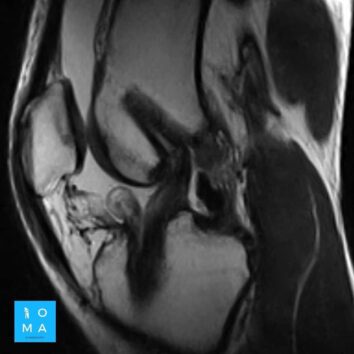

En la evaluación con medio de contraste, se evalúa la relación arterial y de las venas, esto puede servir para buscar la arteria central relacionada con la hiperplasia nodular focal o bien, para evaluar la relación con las estructuras vasculares que son muy importantes para el planeamiento quirúrgico .

en este caso, aún cuando los hallazgos son atípicos tanto para hiperplasia nodular focal como para adenoma, nos inclinamos hacia el diagnóstico de adenoma debido a los antecedentes de la paciente, el tamaño de la lesión, el área de sangrado, el contenido de grasa.